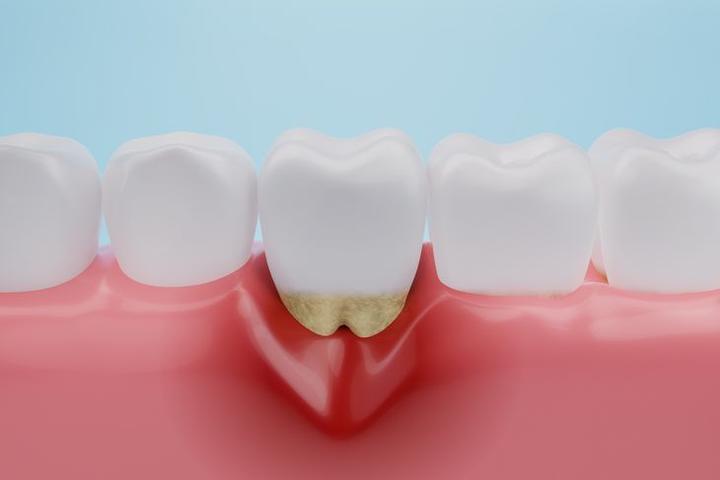

Pacjenci z problemem odsłoniętych szyjek zębowych z pewnością zasługują na naszą uwagę. Najczęściej z tym kłopotem zmagają się osoby w średnim wieku, jednak nie tylko one — również młodsze osoby mogą odczuwać nadwrażliwość i ból przy spożywaniu zimnych lub gorących potraw. Odsłonięte szyjki zębowe stają się nie tylko estetycznym problemem, ale także poważnym wyzwaniem zdrowotnym, które może prowadzić do próchnicy oraz obniżenia komfortu życia. Dlatego w momencie, gdy odczuwasz ból podczas picia ulubionego napoju, warto pomyśleć o wizycie u stomatologa!

Objawami takich kłopotów często są nieprzyjemne reakcje na ciepło, zimno oraz kwaśne potrawy. Można to porównać do włosów — wszyscy możemy je mieć, ale ich zaniedbanie przynosi wiele niedogodności. Odsłonięte szyjki zębowe psują estetykę i prowadzą do wycofywania się dziąseł, co jest prosta drogą do poważniejszych problemów. Właśnie dlatego nie należy bagatelizować tego stanu — im szybciej podejmiemy działania, tym lepsze osiągniemy rezultaty!

Mówiąc o problemach, nie możemy zapomnieć o nadwrażliwości zębów. Kto z nas nie doświadczył tego dramatycznego momentu, gdy przy picu gorącej herbaty ząbkuje nas tak, jakby miał ostry jak brzytwa? Nadwrażliwość to nic innego jak głośny krzyk protestu zębów, które domagają się: „Zróbcie coś z tymi odsłoniętymi szyjkami!”. Co więcej, odkryte części zębów stają się paradoksalnie bardziej podatne na próchnicę, co prowadzi nas do nieuchronnych wizyt u dentysty. Gdy dodatkowo ból pojawia się przy jedzeniu kwaśnych czy słodkich potraw, nie należy czekać – czas udać się do specjalisty!